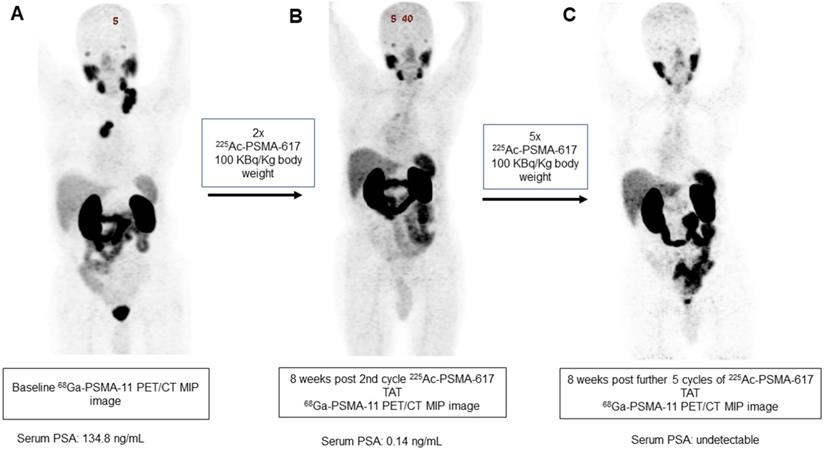

In our patient series, 2 patients achieved clinical, biochemical, and molecular complete remission. In the first patient, a remarkable complete resolution of disease was noted, who was heavily pretreated with standard therapies including 177Lu-PSMA-617 RLT. After receiving 4 cycles of fixed-dose 100 KBq/KgBW 225Ac-PSMA-617 therapy, no grade III/IV toxicities were documented, but the patient experienced fatigue and dry mouth as the main side-effects (Figure 7). The complete molecular and biochemical response was observed in the second patient, in whom the disease was limited to the primary and lymph nodes (Figure 8). This patient received a fixed dose of 100 KBq/KgBW/cycle for 7 cycles. After first two initial cycles of 225Ac-PSMA-617 therapy, 68Ga-PSMA PET/CT scan demonstrated a significant reduction in the cancer burden, revealed residual disease in the mediastinal lymph nodes with fluctuating PSA, hence, further 5 cycles were required to achieve complete biochemical, molecular and morphological response. During the entire treatment course and the follow-up duration, hematological, kidney, and hepatotoxicity were limited to grade I/II. The patient experienced moderate fatigue, which was transient and reduced approximately after 1 week of each cycle of 225Ac-PSMA-617 TAT. The onset of dry mouth symptoms occurred after the 2nd cycle of therapy, which was persistent throughout the follow-up and was grade I/II. At the time of manuscript writing, both the patients are surviving and in complete remission.

A 84-year-old prostate cancer patient treated with hormonal and chemotherapy presented with radiotracer-avid primary disease and lymph node metastasis on pretherapy diagnostic 68Ga-PSMA-11 PET/CT scan (A). After the 2nd cycle of 225Ac-PSMA-617 therapy, the restaging 68Ga-PSMA-11 PET/CT scan revealed a remarkable decrease in the uptake, size, and number of all lesions except for minimal residual disease in mediastinal lymph nodes (B). After further 5 cycles of 225Ac-PSMA-617 TAT, 68Ga-PSMA-11 PET/CT scan demonstrated complete resolution of the lesions (C) consistent with the complete molecular response.

Theranostics Image